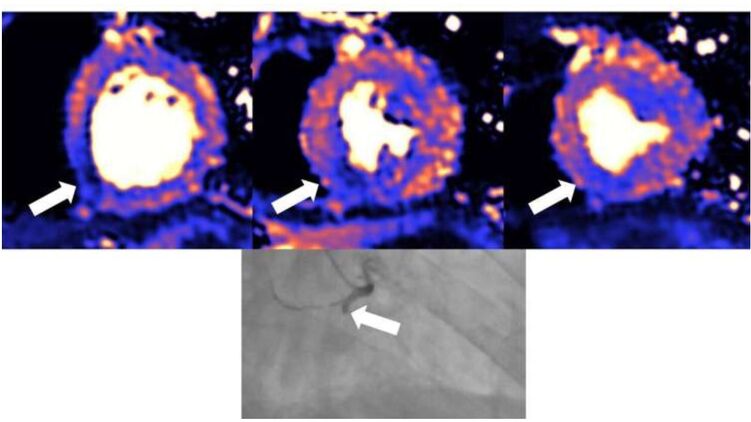

Повреждения сердца выявили при МРТ. Фото: medicalxpress.com

Оказалось, что у тяжелобольных пациентов очень часто наблюдались повреждения сердечной мышцы, которые можно было распознать на снимках спустя 1-2 месяца после выписки. При этом характер травм сердца был неодинаков, что указывает на то, что сердечно-сосудистая система подвержена различным типам воздействий со стороны вируса.

Функция левого желудочка, который отвечает за перекачку насыщенной кислородом крови ко всем частям тела, была нормальной у 89 процентов из 148 пациентов, хотя рубцы или другие повреждения сердечной мышцы присутствовали у 80 пациентов (54 %). Причиной появления рубцов и повреждений стало либо воспаление у 39 пациентов (26 %), либо ишемическая болезнь сердца у 32 пациентов (22 %), либо оба фактора у девяти пациентов (6 %). У 12 пациентов (8 %) воспалительные процессы все еще продолжались.